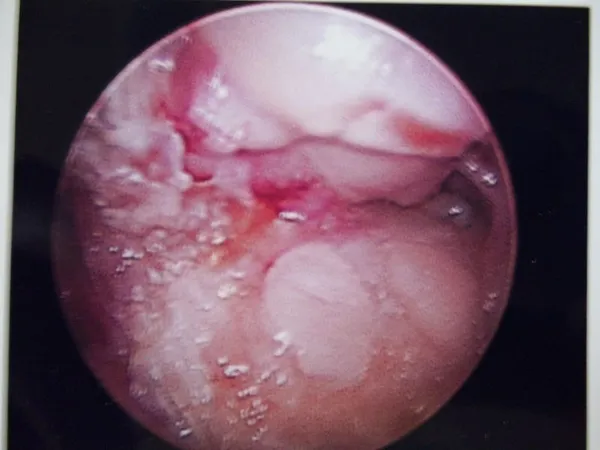

Intraop Pics of Synchondrosis sesamoid fracture

The fracture can be seen. Due to continued pain, a sesamoidectomy was performed. The bone is unhealthy and was removed.